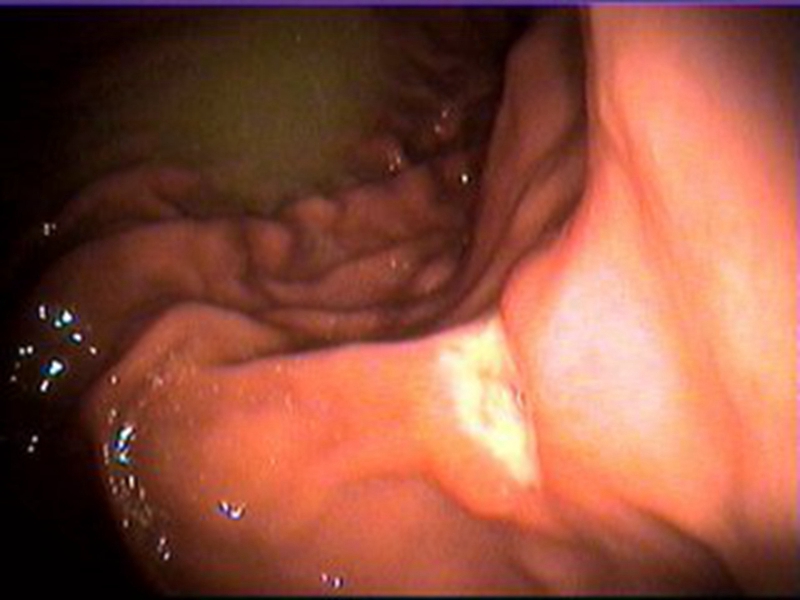

腸腫瘤圖片

直腸腫瘤

直腸腫瘤早期

直腸腫瘤 良性